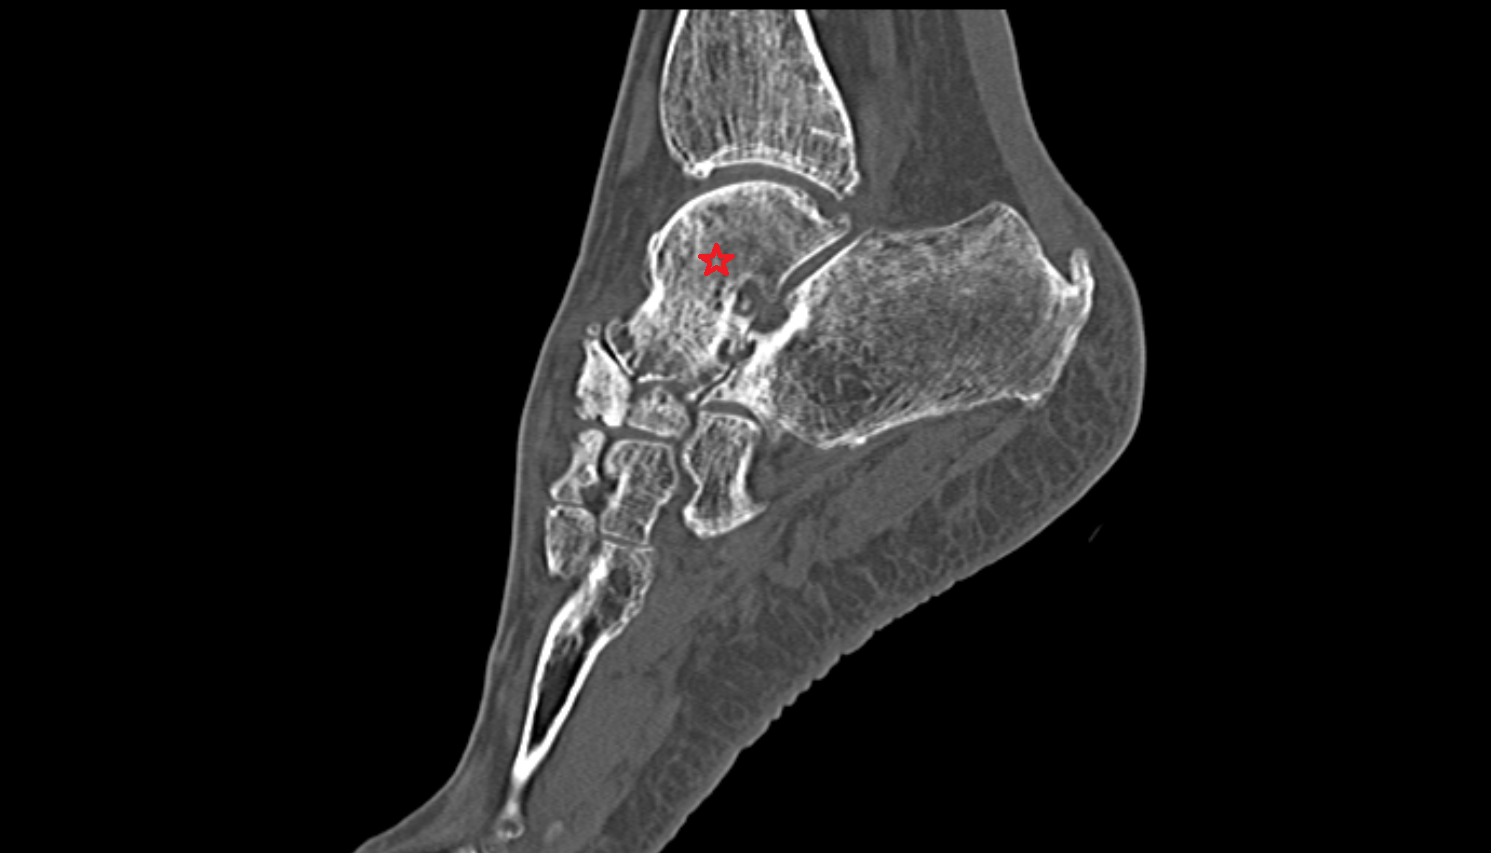

- Talus

- Head of talus

- Body of talus

- Neck of talus

- Calcaneus

- Sustentaculum tali

- Ankle joint

- Talocalcaneal joint